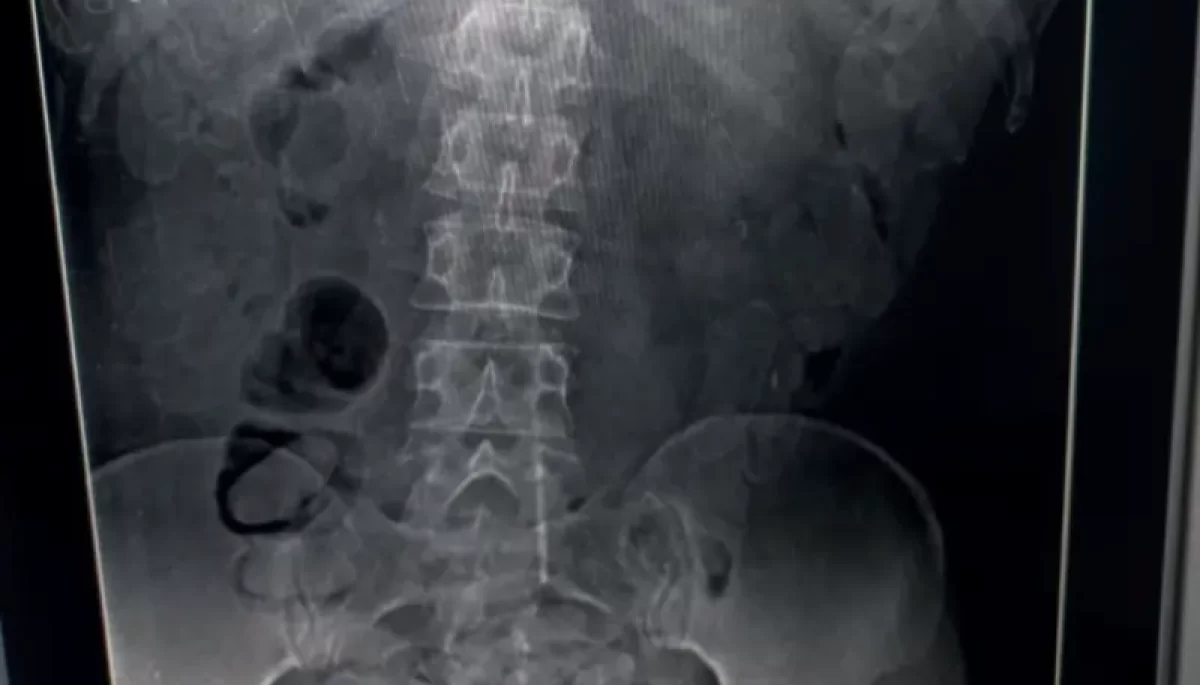

Os bolivianos foram levados ao Hospital de Clínicas (HC) de Marília para exames de imagem e retirada segura das cápsulas. O caso foi registrado na Central de Polícia Judiciária (CPJ), onde os suspeitos permanecem à disposição da Justiça.